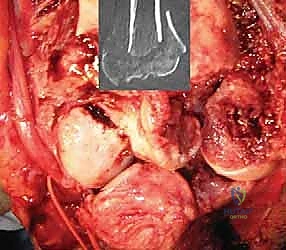

5. تثبيت المفصل النهائي (الإسمنت العظمي)

يتم استخدام المفصل الصناعي النهائي، والذي يتكون غالباً من سبيكة معدنية عالية الجودة (مثل الكوبالت والكروم أو التيتانيوم) مع بطانة من البولي إيثيلين لضمان حركة سلسة. يتم تثبيت جذوع المفصل داخل العظام باستخدام "الإسمنت العظمي الطبي" (Bone Cement) الذي يضمن ثباتاً فورياً وقوياً، وهو أمر حاسم لمرضى هشاشة العظام.

الصور الشعاعية الإضافية والنتائج داخل غرفة العمليات

يحرص الأستاذ الدكتور محمد هطيف على التوثيق الشعاعي الدقيق أثناء وبعد العملية للتأكد من الموضع المثالي للمفصل.